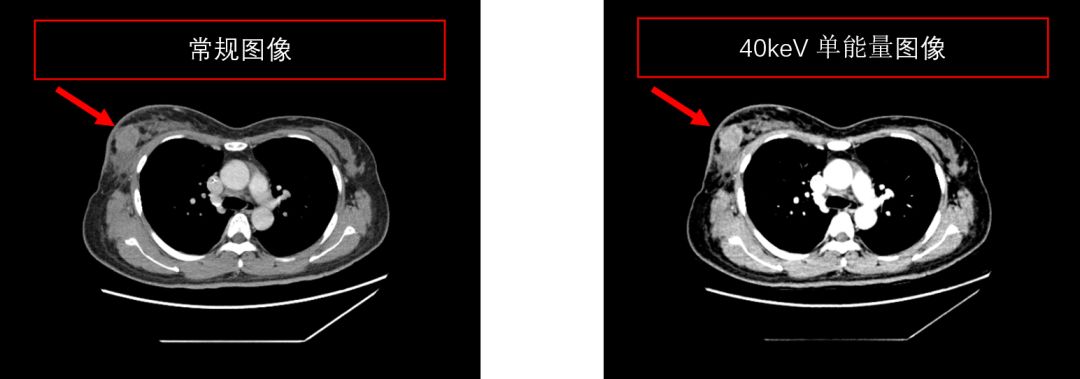

【ct课件】gsi能谱ct成像的临床应用

化疗2个疗程后复查能谱ct提供的单能量技术,可以明显提高肿瘤病灶的

ct课件gsi能谱ct成像的基本原理以及可视化分析工具